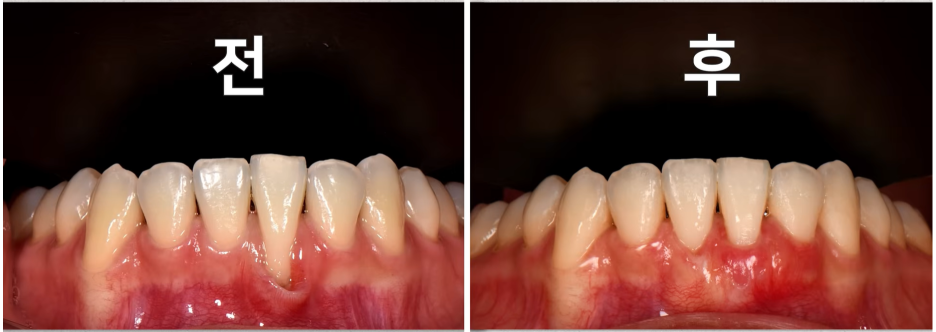

3. 다발성으로 잇몸이 내려앉은 경우

이런 경우도 치료가 가능하다고 합니다.

여러 개의 잇몸이 내려앉았지만 한꺼번에 잇몸을 들어 올려 시술하는 방식으로

"잇몸을 얇게 절개해 들어 올린 뒤 이식조직을 안팎 두 겹으로 감사 지게 하는 방식"이라고 하네요.

출처 - 권의시선 : 치과의사 권낙현 유튜브  여러 개의 잇몸이 한 번에 내려앉은 모습이예요

출처 - 권의시선 : 치과의사 권낙현 유튜브